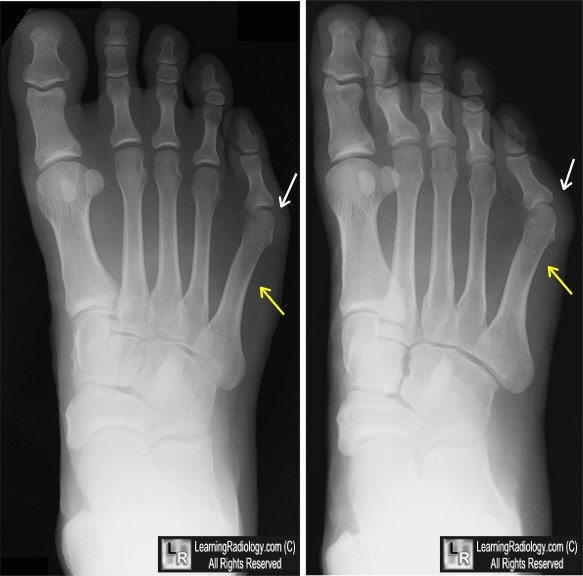

From www.learningradiology.com

LearningRadiology Normal Foot X Ray Vs Bunion Determine whether there is arthritis associated with the bunion. They happen when something pushes your big toe out of its natural alignment and toward your other toes. Bunions are a common foot issue. Eventually, a bony bump can form on the joint. Illustration of foot showing bunion with metatarsus primus varus and normal valgus = 15º vs. Hallux valgus of. Normal Foot X Ray Vs Bunion.